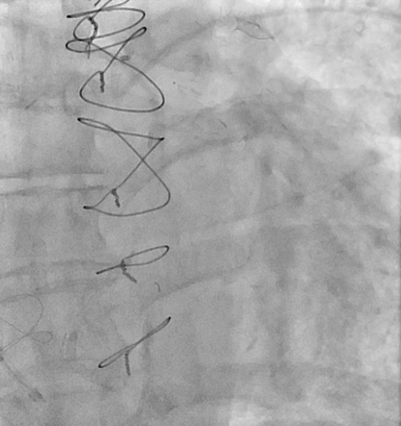

After the right transjugular puncture and introducer implantation, the coronary sinus (CS) was catheterized (Figure, A; Video 1). A CSR was advanced to the targeted implantation site in the mid-segment of the CS. The guiding catheter was then retracted, and the balloon was inflated to expand the CSR at the implantation site. After deflation, the balloon was retrieved. During the extraction of the deflated balloon, under fluoroscopy, we observed device migration into the right atrium while being attached at the tip of the catheter (Figure, B; Video 2). To snare the reducer, a 14-French sheath was advanced in the right femoral vein. We attempted to keep the wire inside the stent, but the prothesis migrated to the left pulmonary artery without the possibility of recovering it using the lasso technique (Figure, C; Video 3). We decided to implant a second CSR more distally in the CS (Figure, D; Video 4).